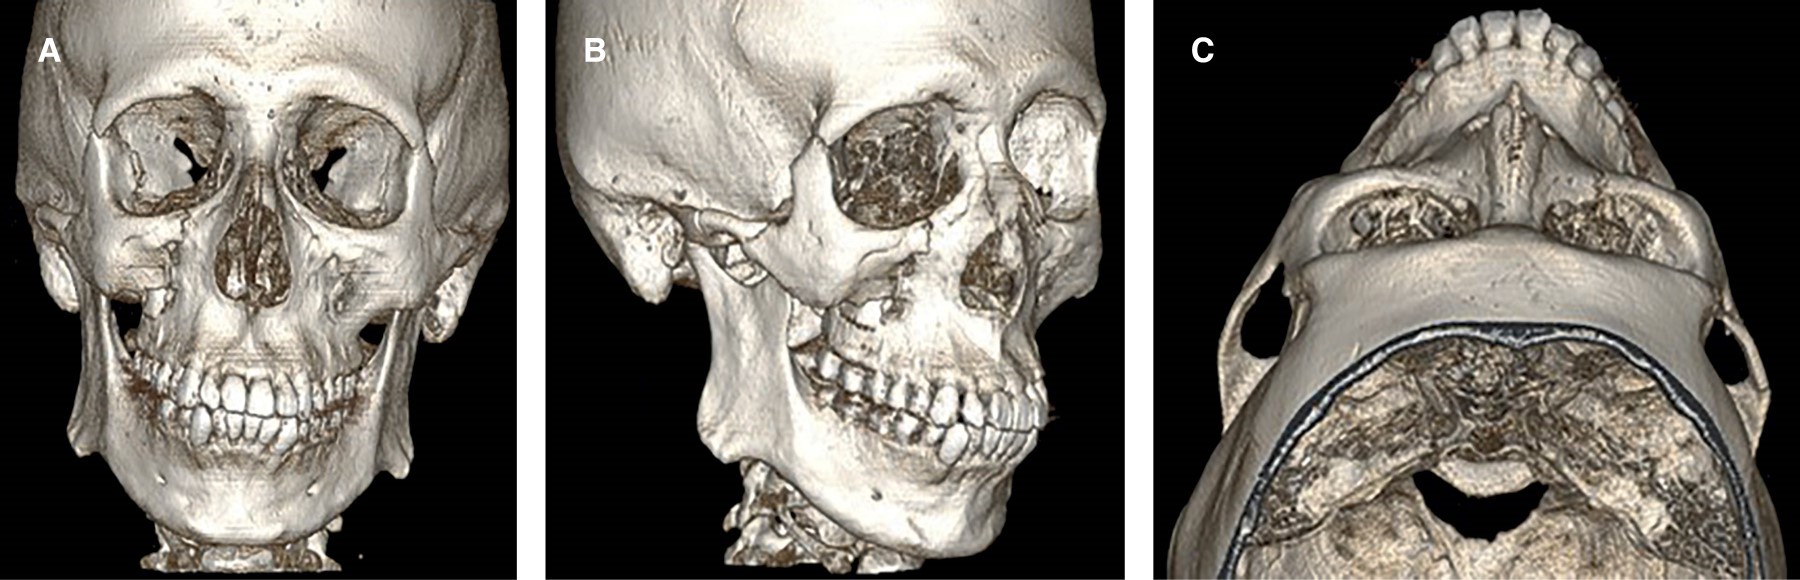

Se realizó tomografía computarizada (TAC) maxilofacial con reconstrucción tridimensional (3D) en las etapas preoperatoria y postoperatoria (a los seis meses de seguimiento). El electrocardiograma evidenció ritmo sinusal. Los exámenes de laboratorio se encontraron dentro de los rangos fisiológicos de normalidad (Figuras 4, 5 y 6).

Fractura orbitocigomático maxilar derecha consolidada. Se consideró como fractura consolidada utilizando los criterios clínicos que presentaba el paciente como ausencia de dolor, inmovilidad de los fragmentos fracturados y buen control de hemostasia. Además, fue relevante la cantidad de días transcurridos desde origen del trauma.

En el presente caso, la falta de reducción temprana generó consolidación en mala posición con limitación del campo visual hacia la derecha y hundimiento malar, acompañado de edema y equimosis periorbitaria. Hallazgos similares han sido descritos por Lu y colaboradores2 y Vahidi y su equipo.7

Para fracturas consolidadas, la técnica indicada corresponde a osteotomías de corrección, mediante cinceles para restablecer la alineación ósea en casos de mala unión.7 Esta intervención resulta esencial cuando existen deformidades estéticas o alteraciones funcionales como la maloclusión. En el caso descrito, el paciente recuperó simetría facial, proyección malar y adecuada oclusión posterior.

Finalmente, a los seis meses postoperatorios, el paciente presentó mejoría del campo visual y proyección malar con resultado estético satisfactorio, corroborado clínicamente considerando la percepción del paciente y por TAC con reconstrucción 3D. Así, incluso en fracturas consolidadas, la osteotomía con fijación en dos puntos permitiría recuperar función y estética.